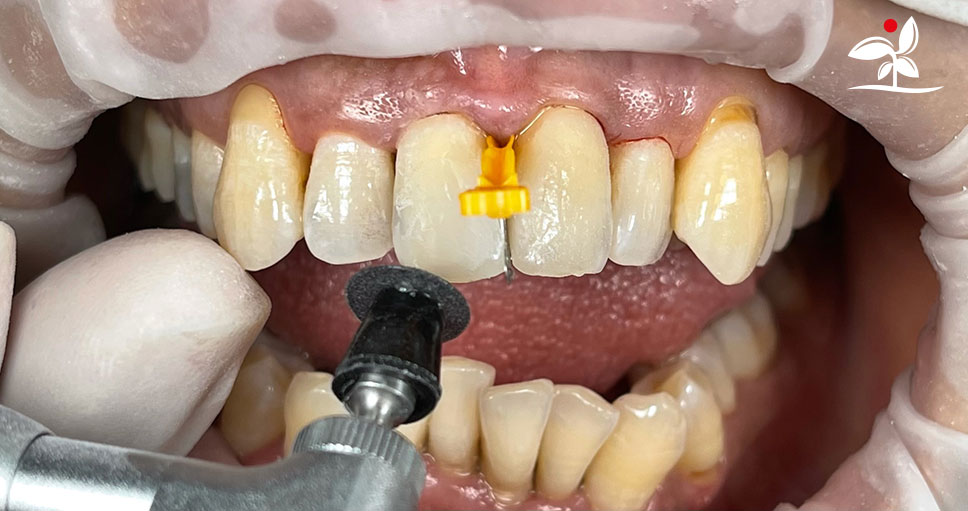

Restoration of Class IV Lesions using Naturomimetic Layering Technique (NLT) and Bioactive Restorative Materials

With the growing awareness about the health, function and aesthetic benefits of preserving natural tooth structure, patients are now globally demanding for aesthetic dentistry with minimally invasive procedures that has a low biological cost. This public demand has encouraged logical clinicians to adopt to the minimally invasive cosmetic dentistry (MiCD) concept and its treatment protocol [1] in their practice. The author has been using MiCD concept and its treatment protocols since 2017, which

include the methods of treatment that are simple, fast, predictable and healthy. In aesthetic restoration, the tooth color restorative materials placement technique is one of the most challenging, confusing and frustrating areas to learn owing to the multiple techniques that have been proposed by many clinicians and replicating such techniques in practice is not always as easy as they are marketed in dentistry. Natural teeth are complex in structure and hard to simulate due distribution of colors through enamel and dentin [2]. Aesthetic restoration strategies should follow proper understanding of defects, right selection of restorative materials along with their proper application, finishing, texturing and polishing [2].